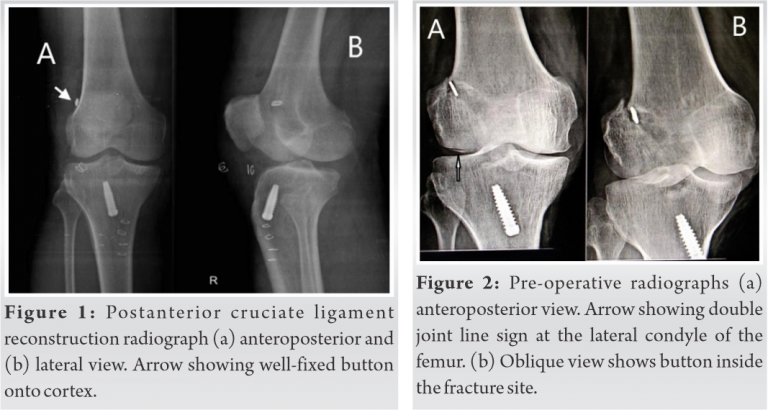

A 41-year-old male, Kabaddi player, presented to Pravara Rural Hospital, Loni in January 2021 with right knee instability of 6 months duration, positive Lachman test, complete ACL tear and medial meniscus posterior horn Grade III tear on magnetic resonance imaging (MRI). He was treated with arthroscopic ACL reconstruction using semitendinosus and gracilis (HT) graft fixed with 15 mm closed-loop button on the femur and 25 mm × 8 mm titanium screw on the tibia and medial meniscus balancing. Post-operative radiographs confirmed well-fixed button and good tunnel positions (Fig. 1). The patient was started on knee rehabilitation, closed chain exercises, and full weight-bearing.